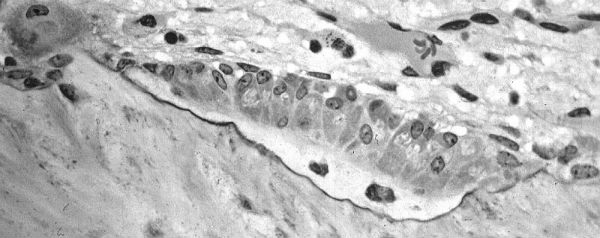

Door de software van Google Maps te gebruiken, kunnen onderzoekers kijken naar de verbindingen tussen verschillende weefsels. “Dit was op zich al eerder mogelijk, maar alleen voor heel kleine stukjes weefsels. Nu kan dat voor hele organen”, mailt hoofdonderzoekster Melissa Knothe Tate.

Zo heeft het onderzoeksteam van Knothe Tate gevonden dat bij osteoporose de verbindingen tussen de cellen stukgaan in verschillende weefsels in de knie. “Dit is iets wat we nog niet eerder hebben kunnen doen: het verbinden van de gezondheid van de cellen aan een ziekte zoals osteoporose”, legt Knothe Tate in een filmpje uit.

De universiteit heeft een stukje voorbeeldweefsel online geplaatst. Alleen dit kleine stukje heupweefsel is al opgebouwd uit 2 miljoen beelden. Hierdoor hebben de onderzoekers vele terabytes aan data.